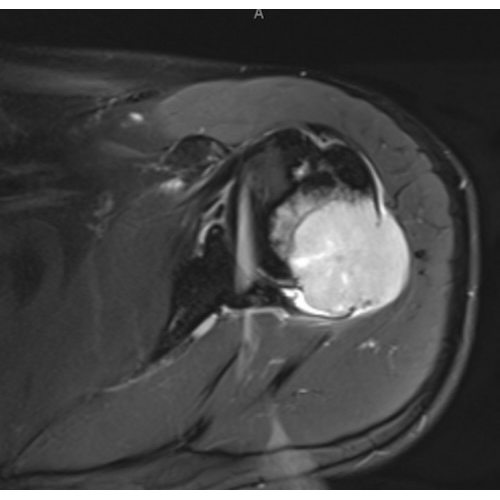

| Lurking In The Acoustic Shadows: Uncovering An Uncommon Diagnosis With Ultrasound - Page #3 | |||